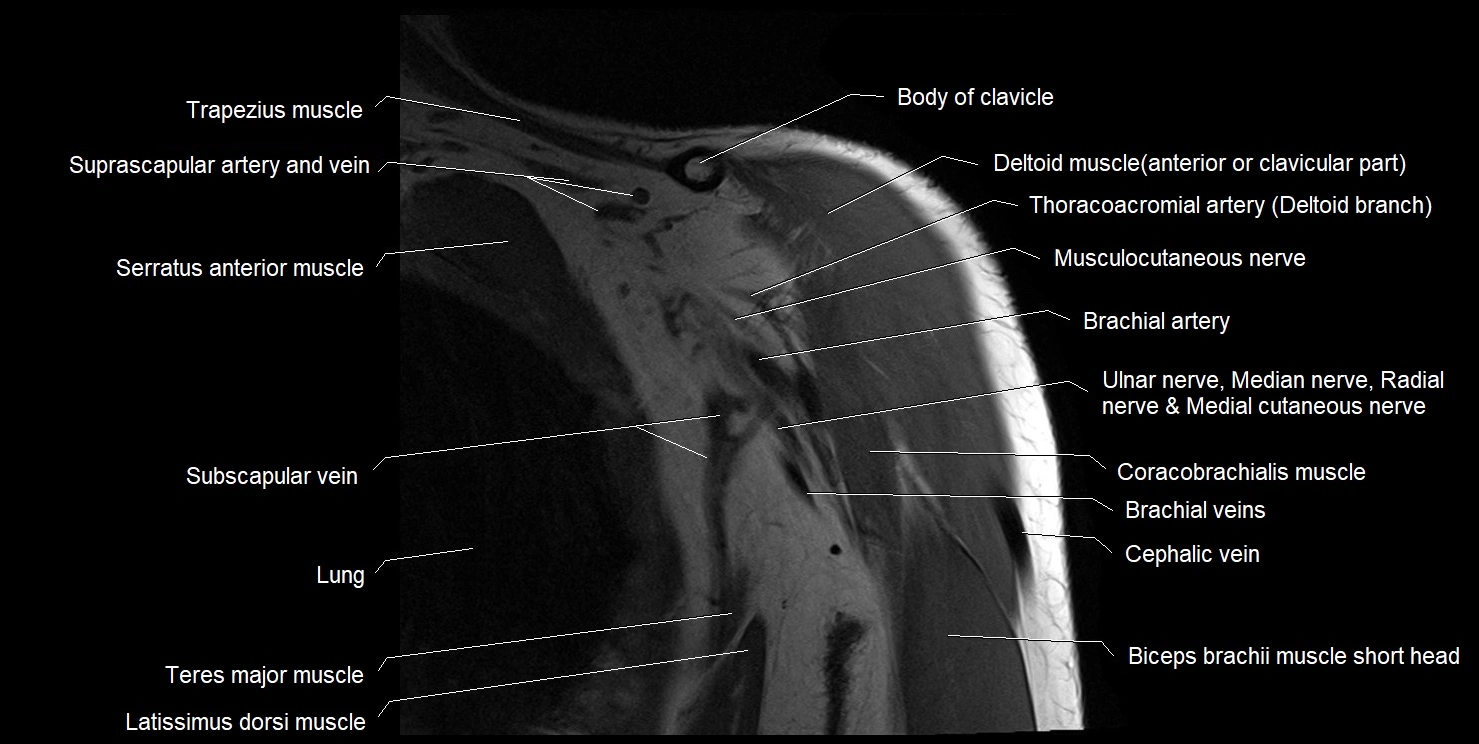

CT image

image